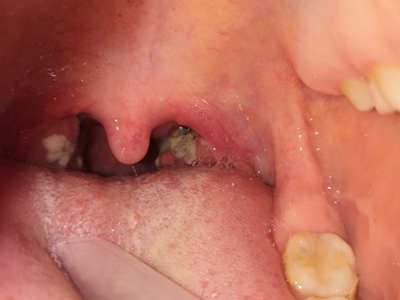

化脓性扁桃体炎单侧扁桃体变大化脓图

化脓性扁桃体炎咽部单侧扁桃体肿大突出,颜色呈鲜红色,形状不规则,黏膜表面凹凸不平,附有黄白色物质,伴有明显疼痛等自觉症状。